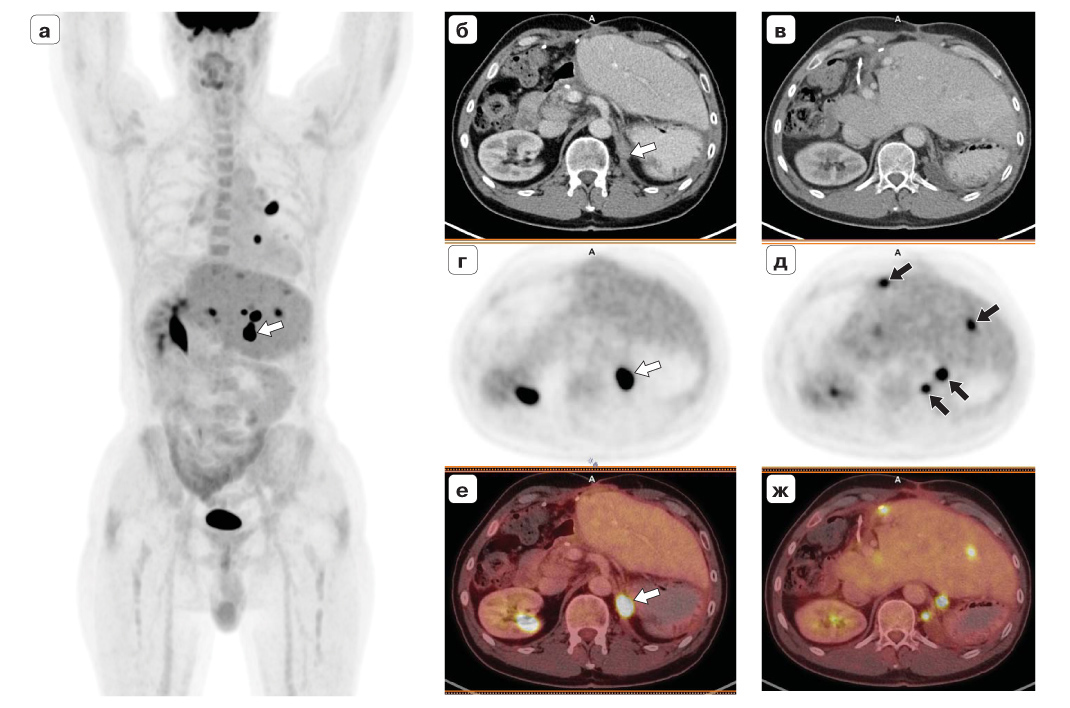

При контрольном ПЭТ/КТ-исследовании от 19.01.2017 определяется очаг патологического накопления РФП в узловом образовании в ложе удаленного левого надпочечника с SUVmax 30,56, размерами до 1,5 см, образование сливается с ножкой диафрагмы. Также определяются множественные очаги патологического накопления РФП в сохранившейся после правосторонней гемигепатэктомии паренхиме печени, в левом легком и в ретрокруральных лимфоузлах, соответствующие метастазам (рис. 2).

Рис. 2. Прогрессирование адренокортикального рака с метастатическим поражением печени, легких и внутри грудных лимфоузлов. Состояние после гемигепатэктомии. ПЭТ/КТ-исследование с 18F-ФДГ. ПЭТ (MIP) во фронтальной проекции (а), КТ с внутривенным контрастным усилением (б, в), ПЭТ (г, д) и ПЭТ/КТ (е, ж) в аксиальной проекции. Объемное образование в ложе левого надпочечника (белые стрелки), метастазы (черные стрелки).

2. Рис. 2. Прогрессирование адренокортикального рака с метастатическим поражением печени, легких и внутри грудных лимфоузлов. Состояние после гемигепатэктомии. ПЭТ/КТ-исследование с 18F-ФДГ. ПЭТ (MIP) во фронтальной проекции (а), КТ с внутривенным контрастным усилением (б, в), ПЭТ (г, д) и ПЭТ/КТ (е, ж) в аксиальной проекции. Объемное образование в ложе левого надпочечника (белые стрелки), метастазы (черные стрелки).